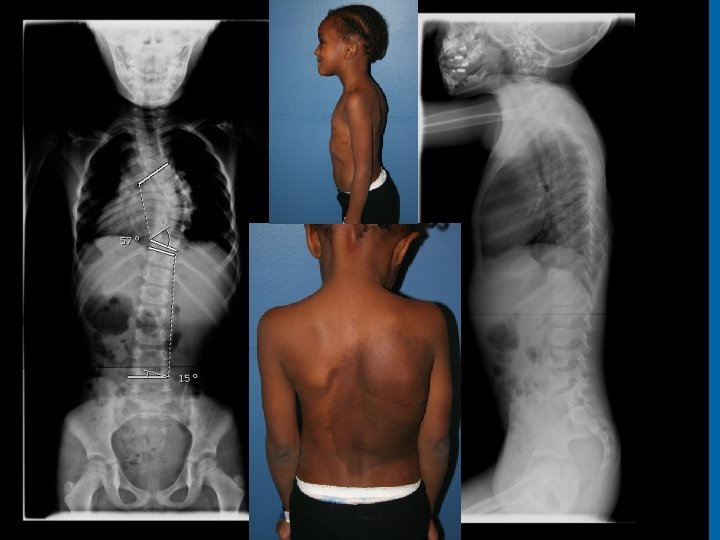

NF 1 and Dural Ectasia • Frequently thoracic • Can be relatively protective, increased SAC • Posterior scalloping commonly associated with dural ectasia • Lateral and anterior scalloping commonly result of primary mesodermal dysplasia • Tsirikos AI 2004 • Anterior dural ectasia and dislocation of the spine • Winter 1991 28

Modi HN 2009 De Kleuver M 2004 29